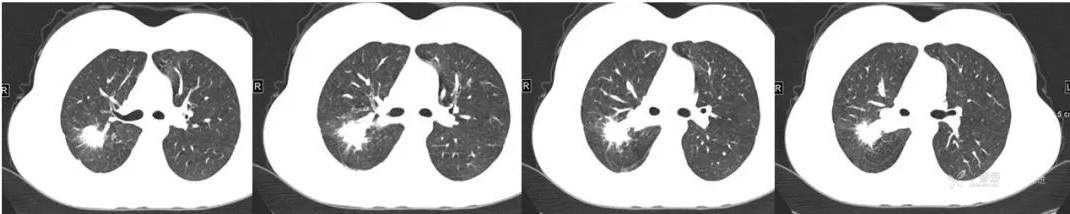

主诉:发现肺部病变1年余

简要病史:患者体检发现右上肺不规则结节影,周围可见小结节影,右肺门及纵隔内多发肿大淋巴结影,当时患者临床无明显症状,支气管镜检考虑结核可能性大。完善T-SPOT阳性,予以诊断性抗结核治疗,肺部病灶吸收好转,9个月后在当地医生指导下停药。

又3个月后,患者停药后复查,右上肺结节较前明显增大。现为进一步诊治,遂于今日来我院就诊。